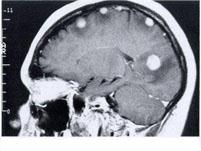

问题 乳癌脑转移时,常用的放射剂量为()

选项 A.25Gy/5次/1周 B.20Gy/5次/1周 C.10Gy/次 D.50Gy/25次/5周 E.30Gy/10次/2周

答案 E